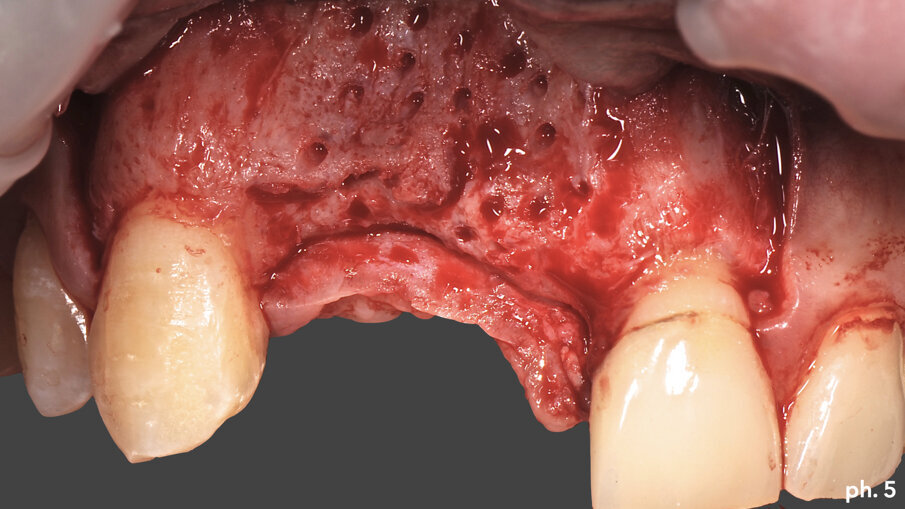

Il paziente, maschio caucasico di 28 anni, si presenta alla nostra osservazione in seguito a un incidente che ha provocato l’avulsione traumatica degli elementi 1.1 e 1.2 con conseguente riduzione dei volumi ossei della zona che, oramai, risulta parzialmente edentula. Sono inoltre presenti in corrispondenza degli elementi 2.1 e 2.2, anch’essi coinvolti nel trauma, due elementi provvisori in resina. La richiesta del paziente è quella di riabilitare la zona edentula con impianti e finalizzazione protesica da 1.2 a 2.2 con corone singole in ceramica1, 2. Dall’esame clinico si evidenzia una carenza di tessuto osseo sia in senso verticale (Fig. 1) che in senso orizzontale (Fig. 2). Si è deciso quindi che l’opzione terapeutica migliore per ottenere una buona rigenerazione ossea di tipo combinato, fosse quella di utilizzare una griglia in titanio customizzata3 in combinazione con un mix di osso bovino deproteinizzato (Geistlich Bio-Oss) e chips ossei prelevati nella zona operata tramite l’utilizzo di un un safe-scraper (Meta)4, il tutto ricoperto da uno strato di matrice Mucograft. Il protocollo operativo delle griglie in titanio customizzate Yxoss CBR prevederebbe l’utilizzo di una membrana in collagene come Geistlich Bio-Gide nella ricopertura della stessa. Personalmente in alcuni casi da me trattati ho deciso di sostituire la membrana in collagene con la matrice, sempre in collagene di origine suina ma in questo caso ricostituito, soprattutto nei settori estetici laddove è richiesta una maggiore quantità di tessuto cheratinizzato al fine di ottenere un risultato estetico migliore. Una volta esposto quindi il tessuto osseo (Figg. 3, 4), si è provveduto ad effettuare una serie di perforazioni a livello della corticale ossea al fine di favorire un regolare sanguinamento (Fig. 5): questo permetterà ai nostri materiali da rigenerazione di usufruire di una maggiore quantità di fattori di crescita, proteine morfogenetiche, ed ottenere quindi una loro migliore integrazione nel tempo.

Una volta riempita la griglia con il mix di osso eterologo e autologo, la stessa è stata posizionata a livello del difetto e stabilizzata tramite l’utilizzo di viti di fissazione autofilettanti (Figg. 6, 7). Il grado di stabilità di queste griglie in titanio customizzate CAD/CAM è assolutamente elevatissimo, così come il loro grado di precisione. Stabilizzata in maniera perfetta la griglia, la stessa è stata ricoperta con uno strato di Geistlich Mucograft in modo da permettere la miglior maturazione possibile dei tessuti molli in fase di guarigione (Fig. 8). Al momento della chiusura del lembo è stato necessario effettuare un’incisione per il rilascio del periostio per ottenere una guarigione per prima intenzione, aspetto fondamentale affinché la maturazione di tali presìdi risulti perfetta. Il tempo di guarigione suggerito dalla letteratura prima della rimozione della griglia è di circa otto mesi; personalmente aspetto sempre 12 mesi prima di inserire impianti in una zona di osso rigenerato, e così è stato anche in questa situazione. L’immagine numero 9 rappresenta la guarigione a un anno di distanza e la relativa radiografia di controllo (Fig. 9). L’attesa così prolungata porta a far sì che la fase chirurgica della rimozione delle griglie in titanio sia l’aspetto più complesso di tutto il trattamento. Questo perché le aderenze di tipo fibroso che si creano tra i tessuti molli e la griglia stessa rendono difficile l’asportazione soprattutto a livello palatale e linguale (Fig. 10).